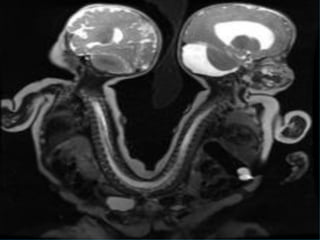

ÓRGÃOS PÉLVICOS

FEMININO

MASCULINO